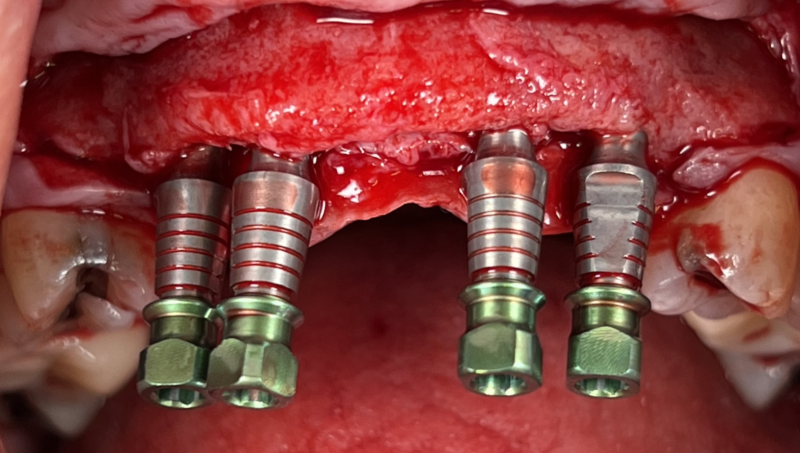

I want to share a case I’m particularly proud of. My homie AJ Marbeh in San Diego took this case from start to finish. After taking the online GBR course by David Wong he crushed it with this difficult case and he used Implant Club fixtures. Brings a tear of happiness to my eye. LOL but seriously, Love this case!